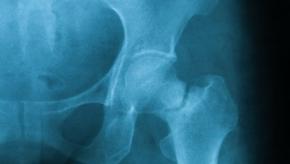

Fractures

Read ArticleOsteoporotic Fractures as Back Pain in Older Men

The Journal of Bone and Mineral Research reports that older men with undiagnosed vertebral fractures are likely to report new or worsening back pain. (Citation source bit.ly/2y9rMiZ)

Read ArticleRomosuzumab Followed by Alendronate is Best in Fracture Prevention

The NEJM reports that in high risk post-menopausal women, romosozumab for 12 months followed by alendronate resulted in a significantly lower fracture than alendronate alone.